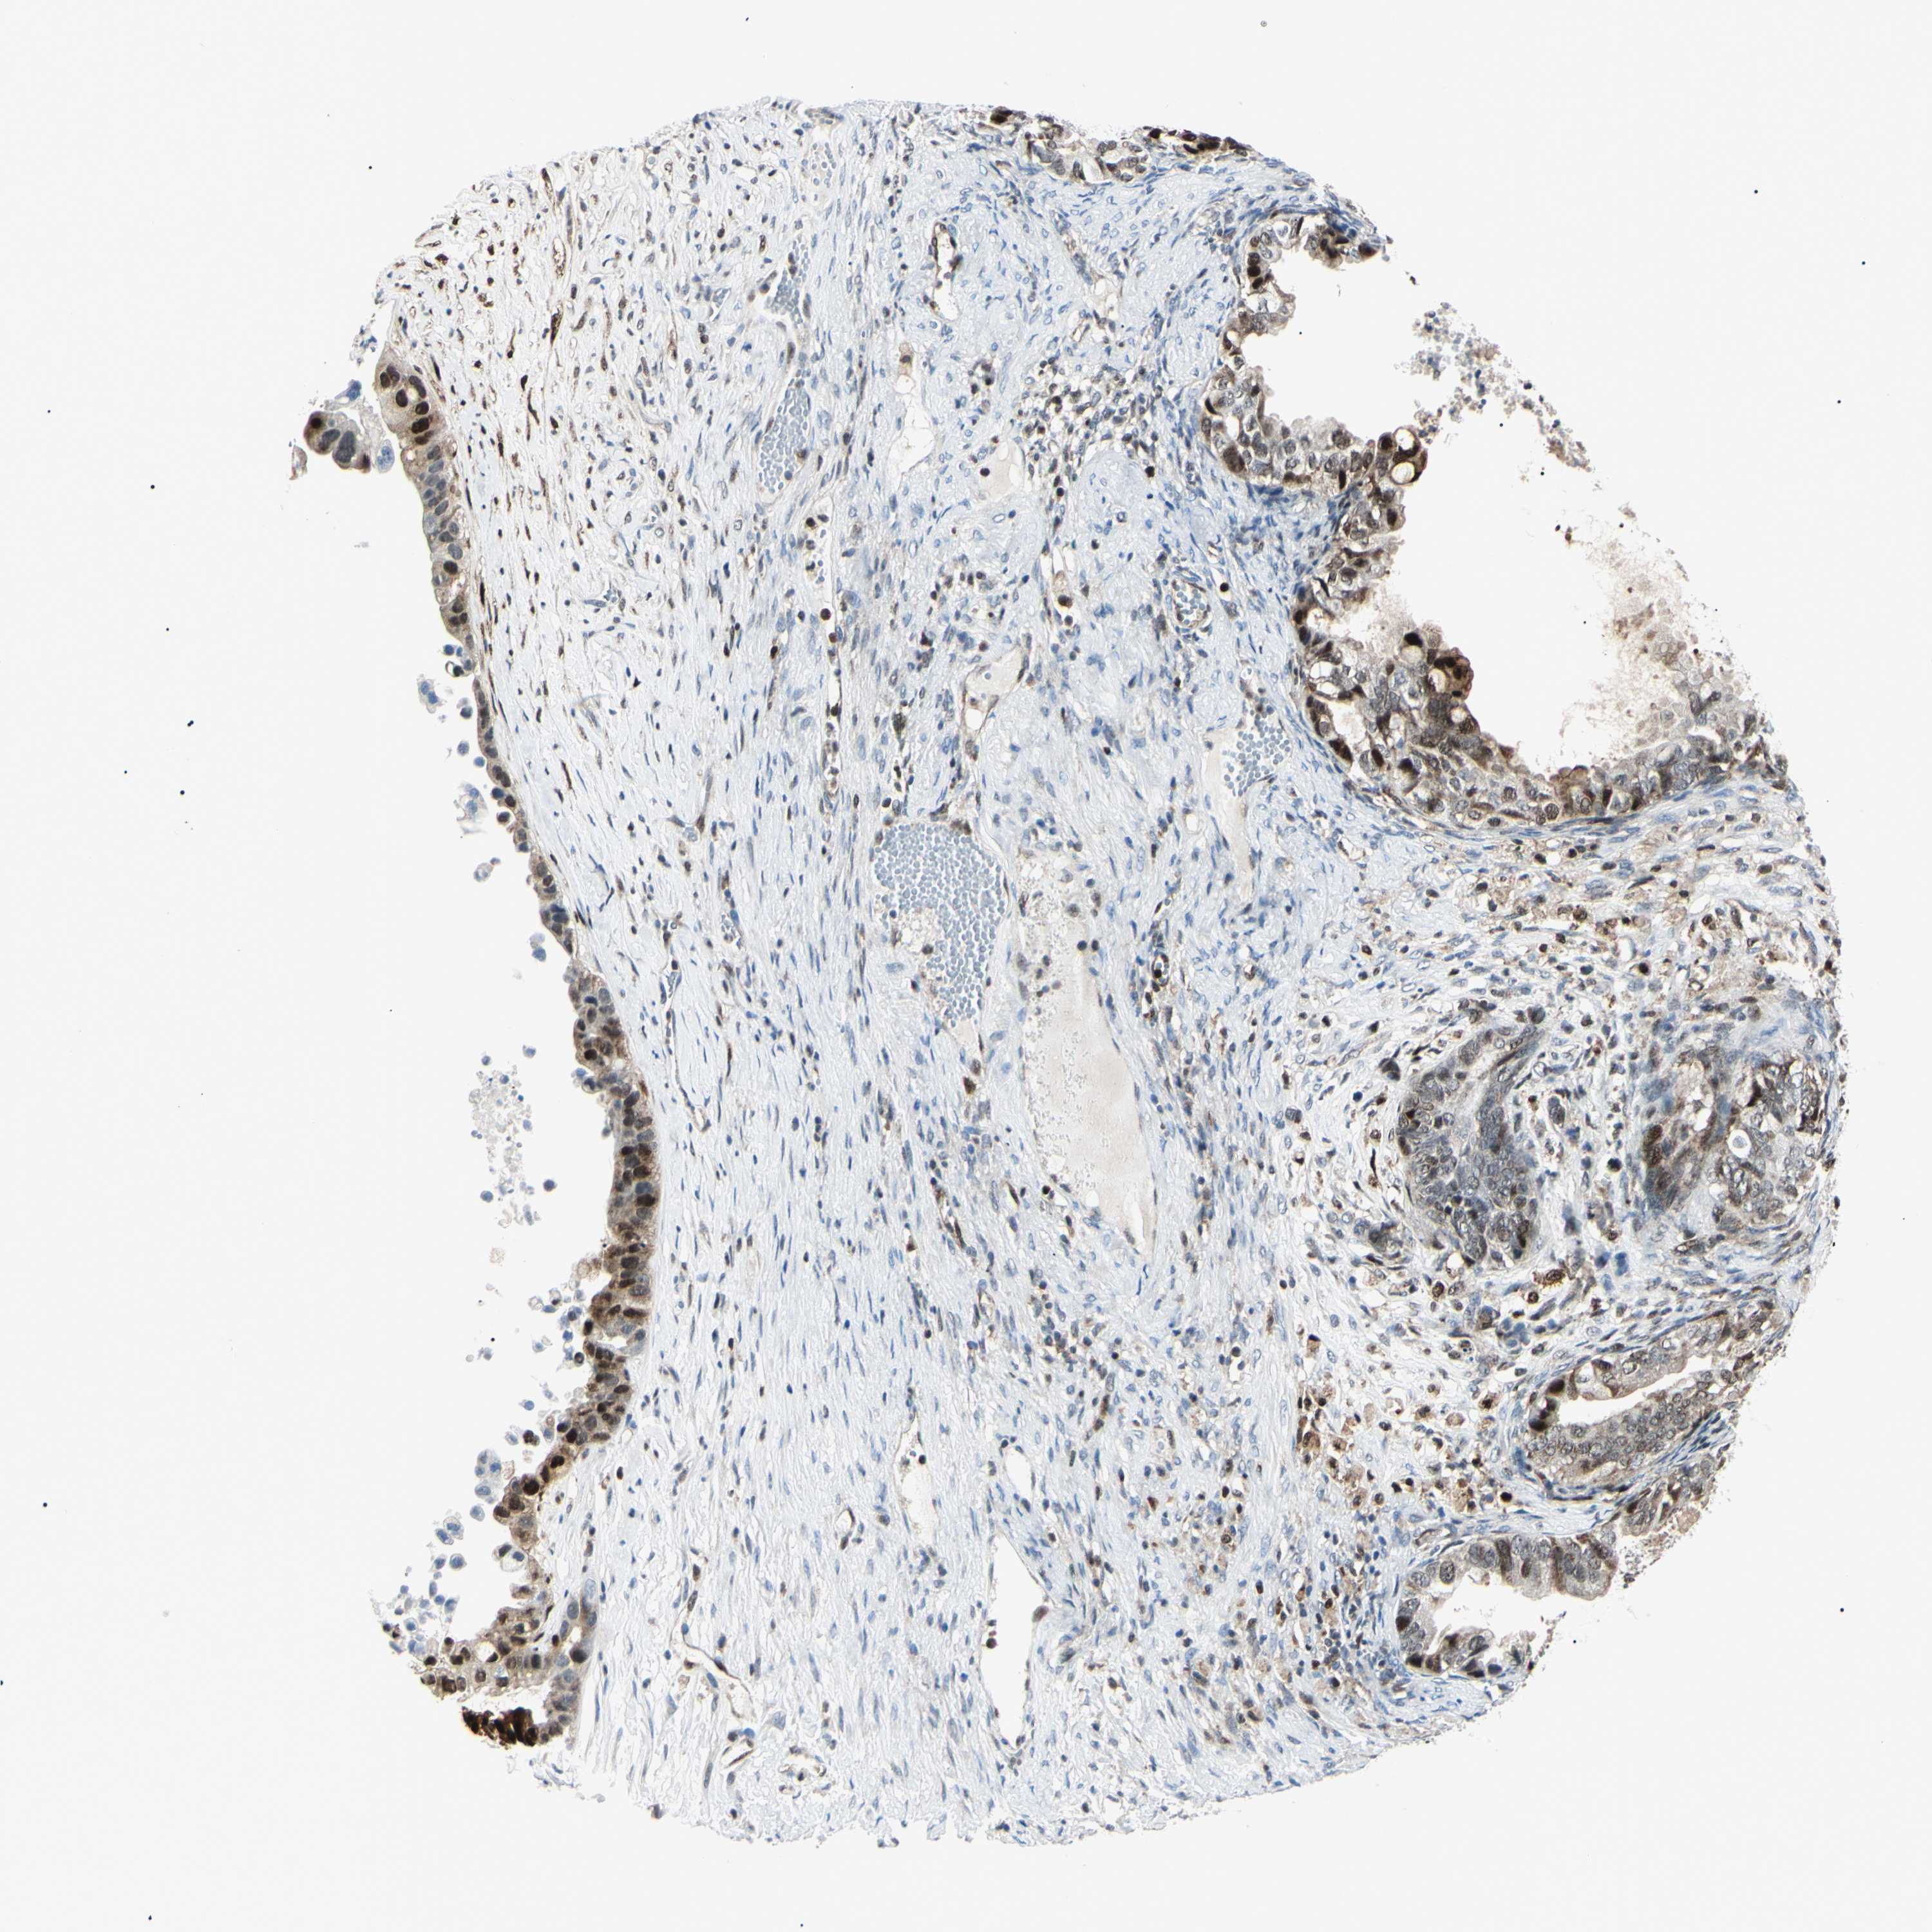

OVARIAN CANCER - Protein expressioni

A mouse-over function shows sample information and annotation data. Click on an image to view it in a full screen mode. Samples can be filtered based on level of antibody staining by selecting one or several of the following categories: high, medium, low and not detected. The assay and annotation is described here.

Note that samples used for immunohistochemistry by the Human Protein Atlas do not correspond to samples in the TCGA dataset.

Antibody stainingi

Antibody staining in the annotated cell types in the current human tissue is reported as not detected, low, medium, or high, based on conventional immunohistochemistry profiling in selected tissues. This score is based on the combination of the staining intensity and fraction of stained cells.

Each image is clickable and will lead to virtual microscopy that enables deeper exploration of all samples and also displays staining intensity scores, fraction scores and subcellular localization as well as patient and tissue information for each sample.

Antibody HPA045385

Antibody HPA073644

Antibody HPA073656

Antibody CAB010065

Staining

High

Medium

Low

Not detected

Intensity

Strong

Moderate

Weak

Negative

Quantity

>75%

75%-25%

<25%

None

Location

Nuclear

Cytoplasmic/membranous

Cytoplasmic/membranous,nuclear

Cystadenocarcinoma, serous, NOS

Carcinoma, NOS

Cystadenocarcinoma, mucinous, NOS

Carcinoma, endometroid